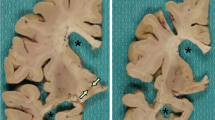

Neuropathologic findings

All five cases showed the same pathologic findings in the same anatomical distribution with some variation in severity (Table 2). Macroscopically, there was mild frontotemporal cortical atrophy. On routine staining, the cerebral cortex showed superficial microvacuolation with neuronal neurofibrillary tangles, in all cases, with patchy frontal cortical status spongiosus (cases 2–5). The tangles ranged from argentophilic cytoplasmic wisps to classical flame-shaped tangles. Immunostaining for phosphorylated tau revealed tangles, pre-tangles (diffuse perikaryal and dendritic immunoreactivity), dot-like immunoreactivity in the neuropil, and neuropil threads (Fig. 2). The tangles, pre-tangles, dot-like lesions and threads were found mostly in the upper cortical lamina and tended to cluster. These changes were extensive but multifocally distributed in discontinuous bands, chiefly involving gyral crowns and less frequently in the depths of sulci. There was no perivascular predilection. Ghost tangles were often found in the superficial lamina. In areas of neocortex with the most tangles, all cortical lamina contained tangles with extensive involvement of pyramidal cells. Tangles, pre-tangles, dot-like lesions and threads were differentially distributed in the cortex. The most severe changes were present in the prefrontal cortex, and the superior and middle frontal gyri. The superior and middle temporal gyri and focally the parietal cortex were extensively involved. The occipital lobe was relatively spared. There was complete sparing of the hippocampus with minimal involvement of the cingulate gyrus, amygdala and hippocampal gyrus.

Histologic findings in nodding syndrome. a Tau-immunoreactive in frontal cortex, mostly in gryal crowns (AT8, scale bar: 1000 μm). b Cortical neurofibrillary tangles (Bielschowsky stain, scale bar: 100 μm). c Neurofibrillary tangles, dystrophic neurites and dot-like immunoreactivity containing phosphorylated tau in cerebral cortex (AT8, scale bar: 200 μm). d Neurofibrillary tangles and dystrophic neurites in neurons in the base of pons (AT8, scale bar: 75 μm)

Globose tangles, pre-tangles and threads were found in various subcortical and brainstem sites (Fig. 2). The tegmental nuclei of the upper brainstem, including the Edinger–Westphal nucleus, substantia nigra, locus coeruleus and the nuclei of the pontine base were preferentially affected. Less extensive formation of tangles, pre-tangles and threads was found in the striatum, lentiform nuclei thalamus and medulla. There was relatively minimal or no involvement of the olives or dentate nuclei. Patchy to extensive Purkinje cell loss with Bergman gliosis and empty baskets in the cerebellum were found in three cases (cases 2, 3 and 5). There was moderate diffuse pallor of myelin staining in one case with preferential involvement of subcortical white matter and the pontocerebellar fibres (case 2). In severely involved areas of neocortex, there were tau-immunoreactive threads in subcortical white matter. Glial cellular inclusions were not prominent in any brain; however, occasional fuzzy/granular astrocytes were found in the locus coeruleus in case 4.